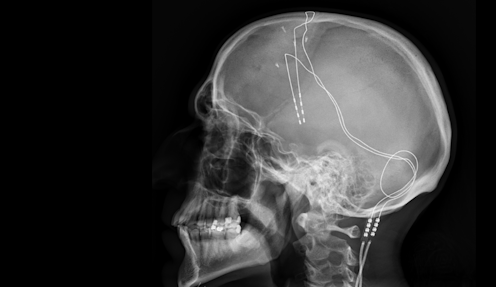

“Deep brain stimulation involves the implantation of electrodes in the deeper areas of the brain,” Davis explains. These electrodes then transfer into the brain itself small electrical currents that a doctor and their patient try to tune correctly. As Davis explains, “Basically we’re looking to find the settings where the patient feels that their mood is better, their anxiety is less and they have more energy.”

Deep brain stimulation works well for a lot of patients and has only started to get mainstream attention in the past decade or so, but ideas underlying this treatment are nearly 60 years old. As explained by Joseph Fins, a neuroethicist and professor of medicine at Wei Cornell Medical College, part of Cornell University in the US, it all started with a Spanish neuroscientist named Jose Manuel Rodriguez Delgado in 1964. “He put a thing called the stimoceiver, a deep brain stimulator, into the brain of a charging bull. And with an electrical current controlled by radio frequency, he was stop the bull in its tracks.”

As modern neuroscience led to better understanding of how the brain works, and stigma surrounding physical treatments faded, deep brain stimulation got its second chance in the sun. And as technology has improved, researchers like Jacinta O'Shea, a neuroscientist at the University of Oxford have begun to study a noninvasive technique for stimulating the brain with electricity, called transcranial magnetic stimulation.